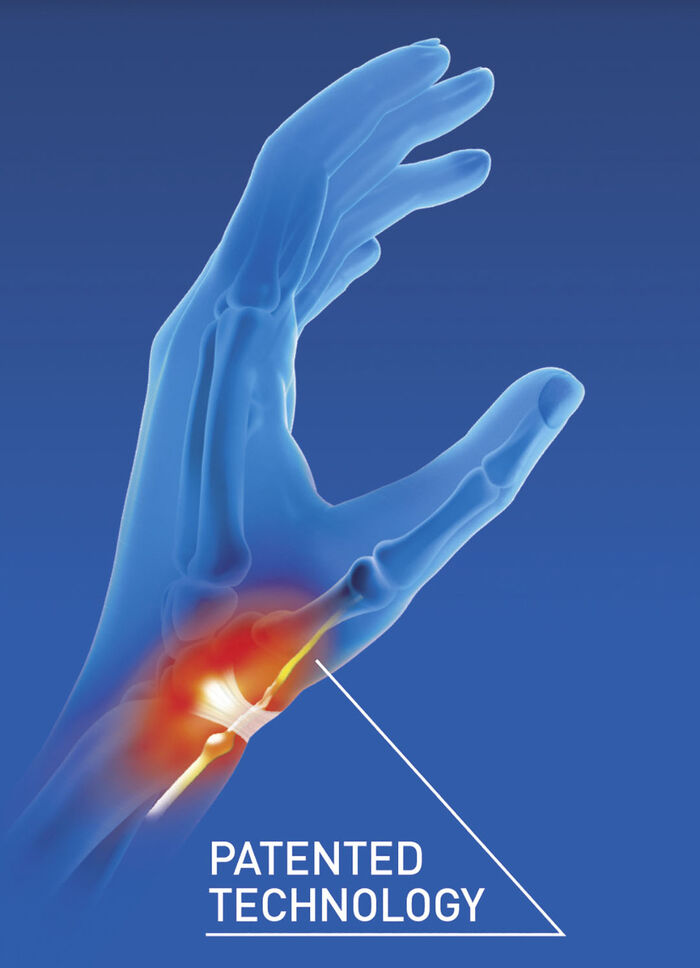

Handgelenkbandage QUERV‘ACTIV™ von EPITACT®